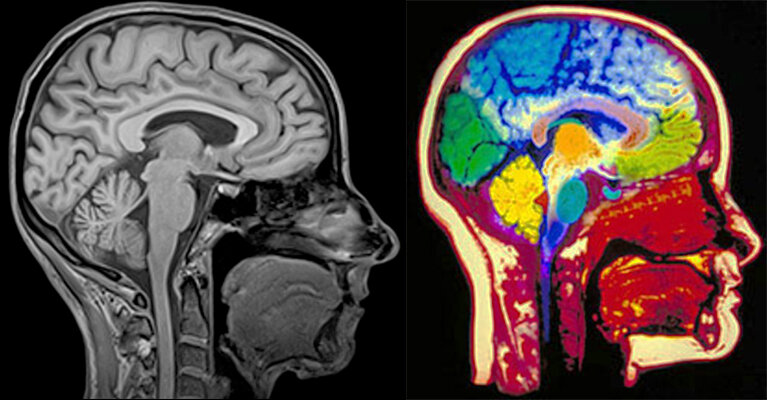

Разница в МРТ с контрастом и без

МРТ с контрастированием подразумевает введение контрастного вещества, которое с током крови распространяется по всему организму. За счет этого отчетливо видны все сосуды. Такая методика позволяет более четко определить структуру, размеры органа. 👇Можно выделить основные отличия в проведении процедур: 1.При контрастировании вводятся специальные вещества в организм человека, только после этого проводится сканирование. Без контрастирования обследование проводится сразу. 2.При использовании контрастного вещества важна подготовка. За 3–5 часов важно отказаться от еды и воды. При проведении простой процедуры особо сложной подготовки не требуется. 3.Продолжительность МРТ с контрастом больше, чем у простой процедуры. 4.Контрастные вещества не используются у беременных женщин. Записаться на консультацию можно по телефону: +7 916 133-85-55 +7 (49-66) 14-05-05 +7 (800-55) 5-65-44 Источник: https://mrtkolomna.ru/